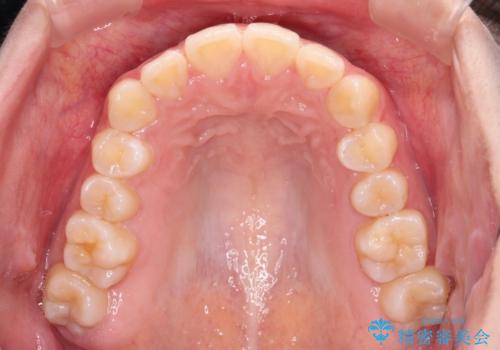

カリエールディスタライザーを併用したことで、確実かつ短期間で治療を終えることができました。

奥歯の咬み合わせを改善しながら、並行してインビザラインで歯列を整えることとしました。